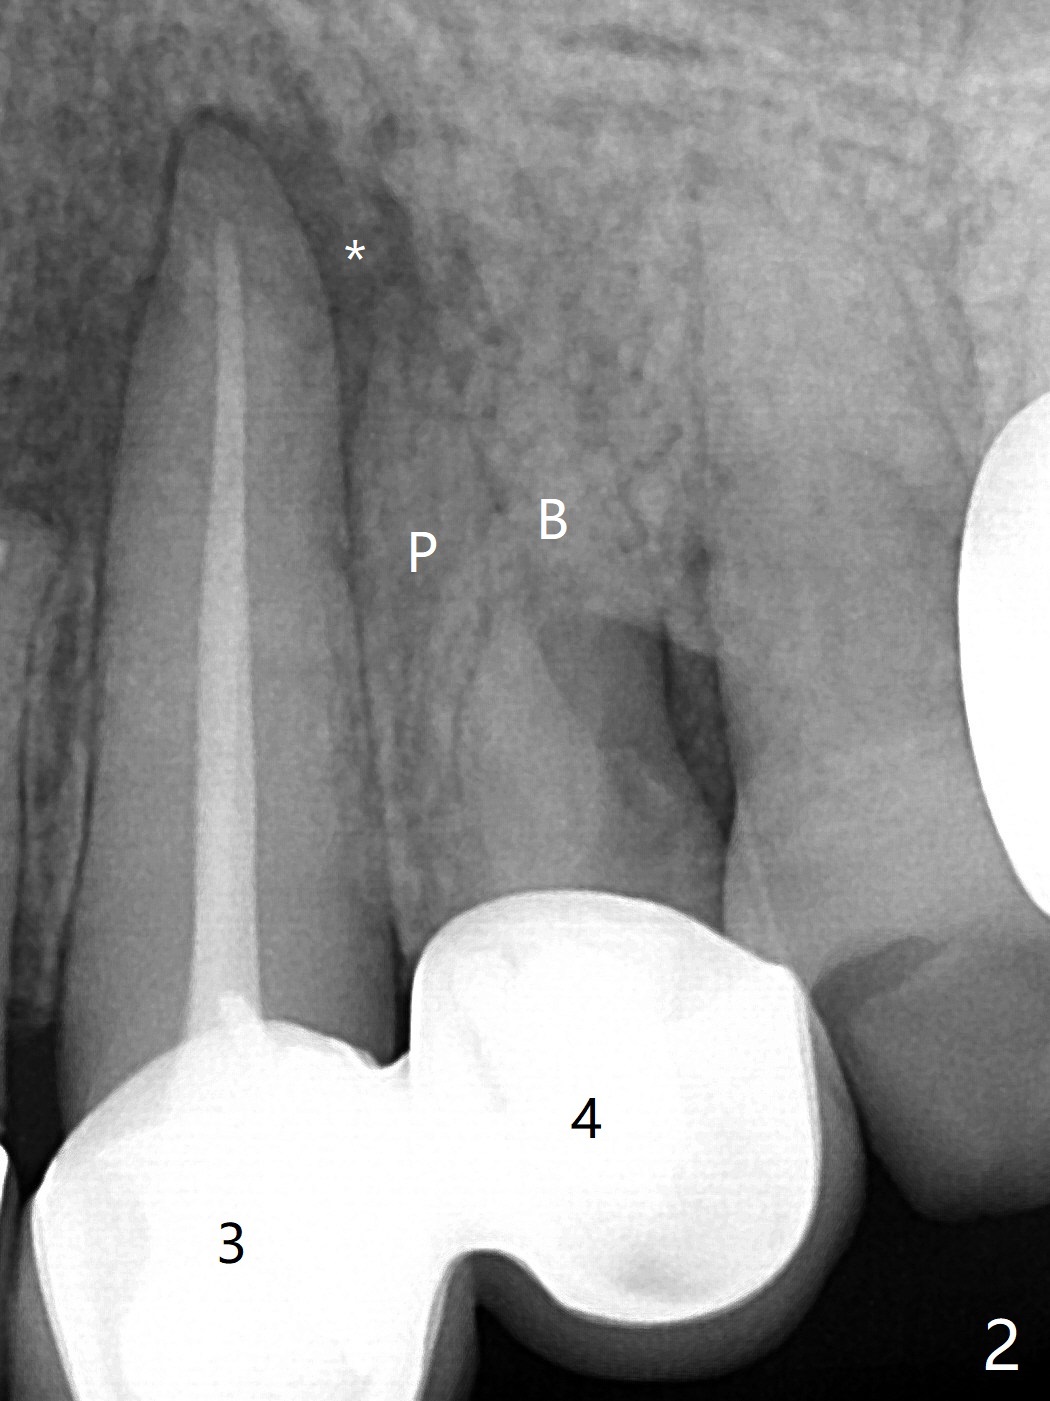

68岁女左上4颊侧瘘道(图一:*),与根尖颊侧骨板缺失相通,其实腭侧根尖周围病变更大(也与颊侧窝相通),术中没有注意腭侧根接近3(图二:P),稀里糊涂的基本顺着腭侧根(颊侧)走向钻洞(图四,与图三理想方向对比),突然记起术前设计钻洞必须在腭侧牙槽窝远中颊侧,在远中建立新洞眼(图五),之后无法再次建立新洞眼,只好利用同一个侧面切割钻头将钻洞往远中移位,同样效果不佳(图六),最后只好放弃,放置粘性骨粉(图七:*),覆盖PRF膜,6个月胶原膜,PGA缝线,牙周胶水。术后重新分析表明顺着腭侧牙槽窝种植与尖牙还是有分离(图八,九:*),因为牙槽窝是斜型的(图十:黑色),不过离颊侧骨板也接近(图八:B)。所以钻洞必须斜型针对远中骨壁,表浅些(图十一:红色箭头);一旦进入骨板,改变角度(图十二:红色箭头),适当矫枉过正,随着植体增大,钻洞会往近中偏移(白色箭头)。最好植体方向理想(图十三)。不过植骨后钻洞偏移可能性比较少。缝线和牙周胶水似乎是一个稳妥固定胶原膜方法。术后病人抱怨水肿严重,术后八天颊侧根尖隆起是由于骨粉推出骨板之外(图十五,十六:*),上颌窦底板无意穿孔(^)伴有上颌窦膜(M)增厚,与术前对比(图十七:上颌窦窦腔清晰)。术后一个月6个月吸收膜不见了,大多数缝线已经脱落,最后两根缝线撤除后,牙槽窝开口已经关闭,好像主要成分是骨粉(图十八)。术后5个月牙槽嵴宽,角化龈也宽,好像可以植入4x11.5毫米植体(图十九)。